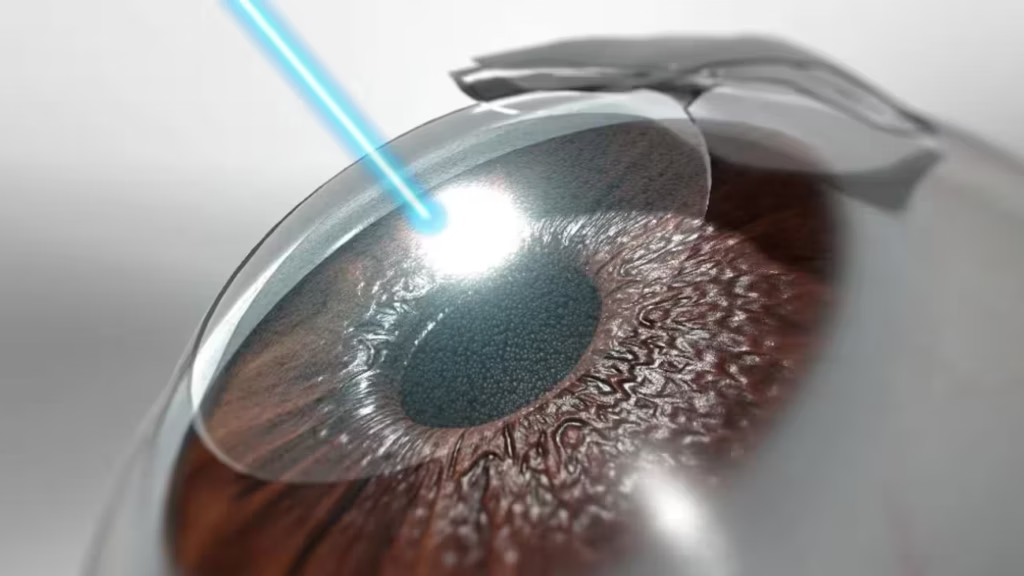

3. Laser Therapy (Photocoagulation)

Laser treatment seals leaking blood vessels and reduces abnormal vessel growth. Focal laser therapy treats macular edema, while scatter or pan-retinal laser therapy prevents proliferation in advanced cases. This procedure can help preserve peripheral vision and prevent further retinal damage.